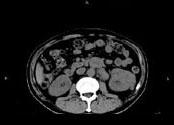

问题 男,65岁,左腰部隐痛不适2个月,CT平扫+增强如图所示,下列说法正确的是 ( )

选项 A、考虑为左肾癌伴肾门淋巴结转移 B、增强扫描可见左肾局部隆起左肾内的病灶强化方式相同 C、腹腔内未见积液,所示骨质亦未见破坏 D、平扫时可见左肾局部隆起,腹主动脉旁、肾门部有等密度的块影

答案 ABCD